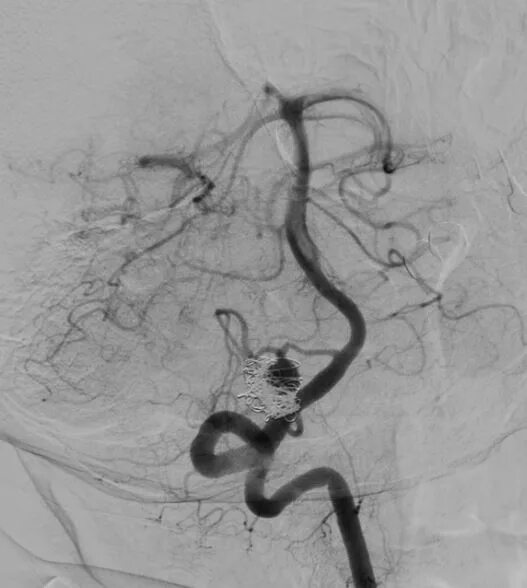

Мешотчатая аневризма внутренней